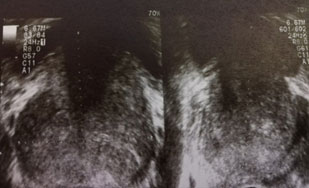

以下超音波と同様に画像の例を提示させていただいております。

画像4:膀胱結石

画像5:前立腺肥大